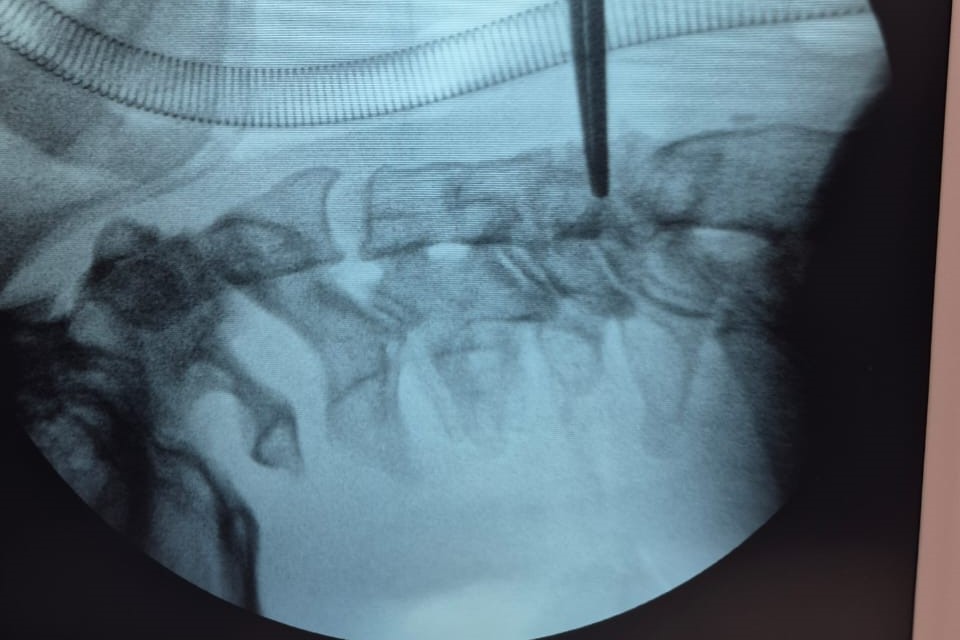

La intervención consistió en una corpectomía cervical, técnica quirúrgica destinada a resolver cuadros severos de compresión medular o radicular mediante la extracción del cuerpo vertebral afectado y su reemplazo por una prótesis especialmente diseñada, provista por el ministerio de Salud, a través de las empresas Zion–Corpomedica.

La corpectomía cervical es una práctica de alta complejidad que requiere precisión milimétrica y equipamiento de última generación. A través de una vía anterior en el cuello, se extrae uno o más cuerpos vertebrales y se reconstruye la estructura ósea mediante injerto o prótesis, liberando la presión sobre la médula espinal.